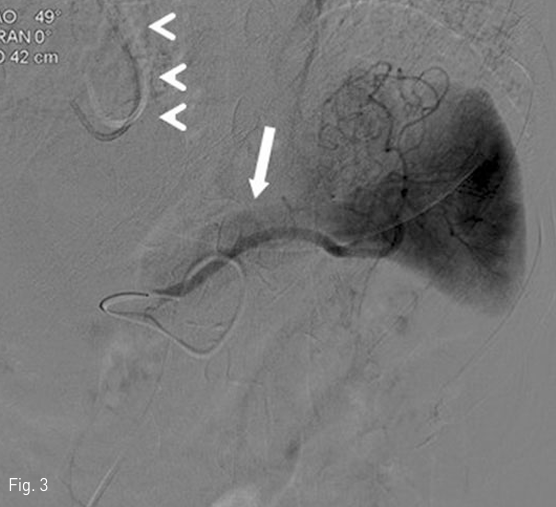

고혈압 병력이 있는 환자로 식후 발생하는 syncope 를 증상으로 내분비내과로 내원 후 시행한 lab 상 endogenous hyperinsulinemia와 hypoglycemia가 있었으며, 이후 시행한 EUS 상 pancreas tail에 19mm 크기의 lobulated mass 소견이 있고, 이는 hypoechoic halo가 동반되어 있는 hypoechoic mass로 관찰됨. 아울러 pancreatic duct의 확장은 보이지 않았음(Fig.1 ).

Fig 1

Endoscopic ultrasonogram shows a hypoechoic nodule (arrow) with hypoechoic halo in pancreatic body.